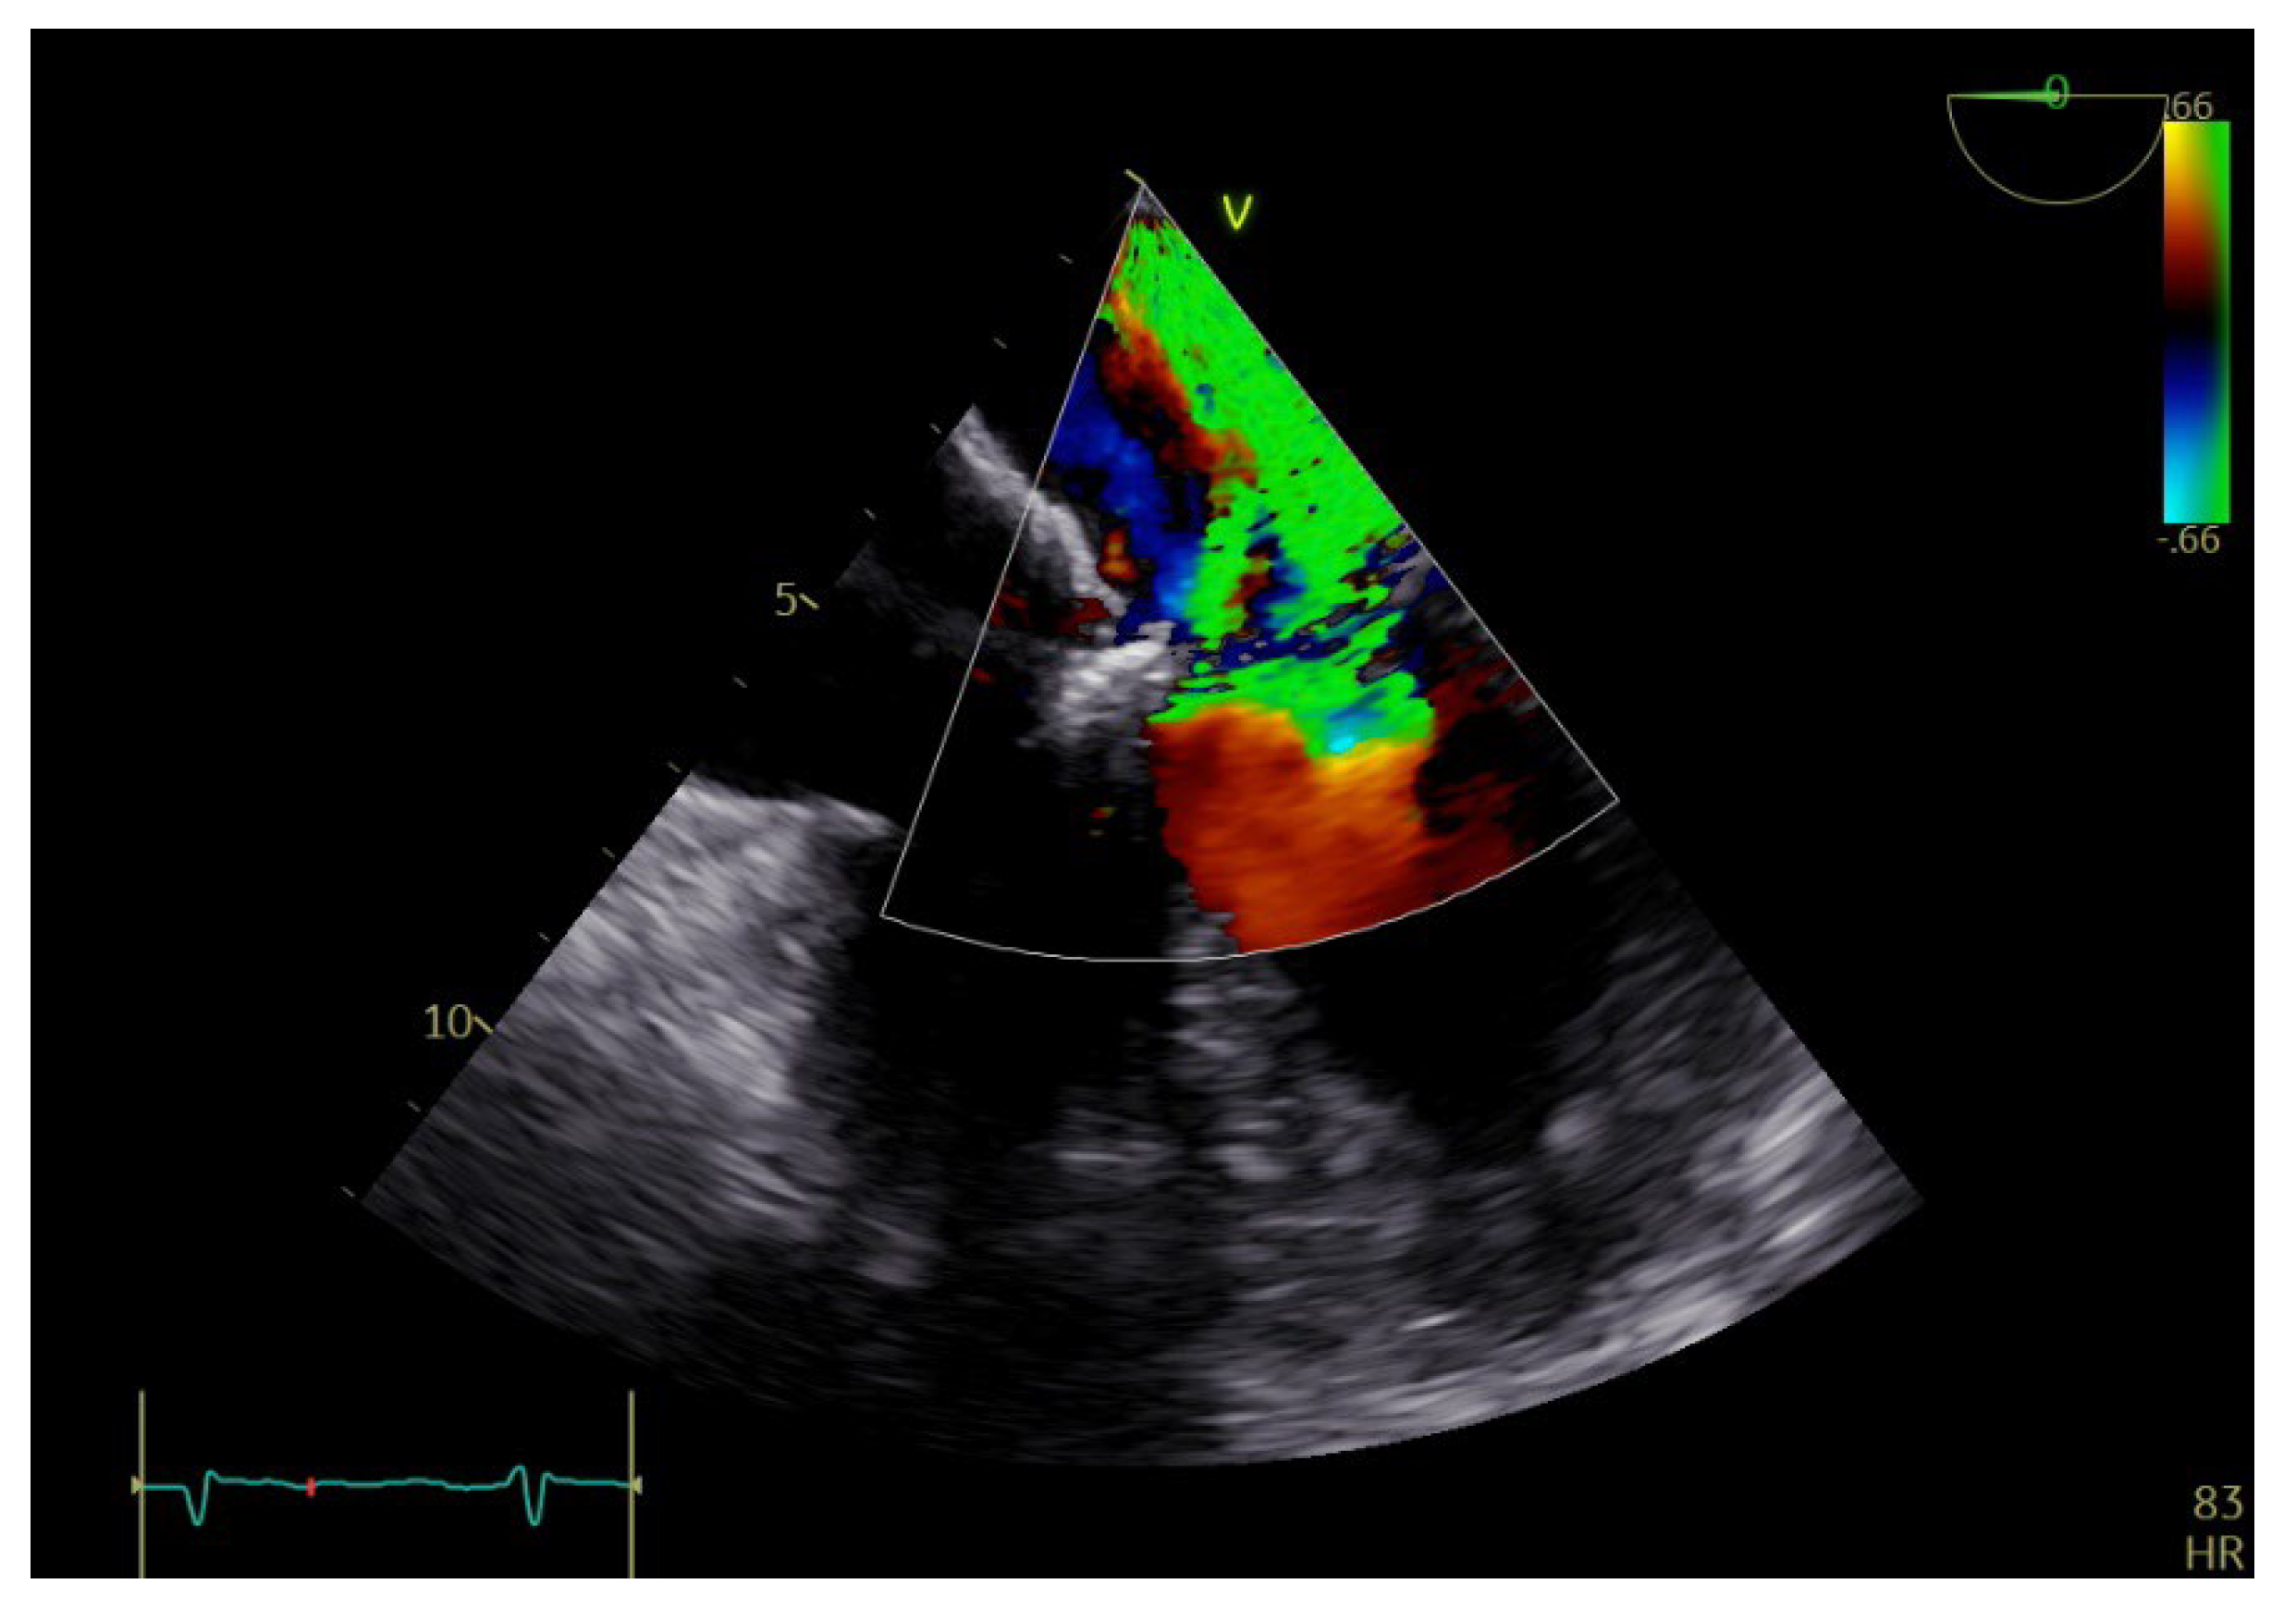

2. Case Report